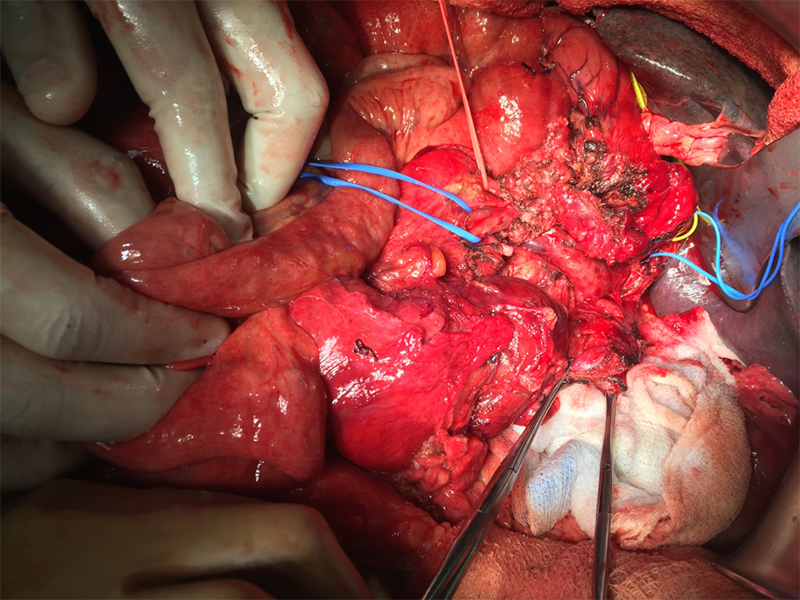

A 54 year old gentleman with long history of alcohol dependence & background of chronic pancreatitis, came with loss of appetite, loss of weight, back / abdominal pain, jaundice and loose motions. On thorough investigations CA 19-9, a tumor marker for pancreatic cancer and bilirubin were significantly elevated. A pancreas protocol computed tomography (CT) of the abdomen revealed a tumor in the head of pancreas in the chronic pancreatitis background. It was compressing / narrowing important gut vein (superior mesenteric vein - SMV). The pancreatic duct and the common bile duct were both dilated due to obstruction. Based on history, tumor markers and CT findings, provisional diagnosis was pancreatic ductal adenocarcinoma (PDAC) with involvement of SMV. There was no sign of any distant metastasis on PET-CT scan. Patient underwent endoscopic ultrasound (EUS) for a biopsy sample. The biopsy confirmed the cancer. A Whiple pancreatoduodenectomy procedure involving removal of cancer bearing portion of pancreas along with part of stomach, bile duct and entire duodenum was removed. Draining lymph nodes were removed. The involved portion of SMV was resected along with pancreas and the vein was reconstructed, a step done in exceptional cases and only by experienced surgeons. Patient recovered uneventfully and was later administered adjuvant chemotherapy. To know more about pancreatic cancer click here

• Involvement of SMV is not a contraindication for surgery, as long as it is possible to reconstruct the involved vein

• Few large volume centers and surgeons have the experience & expertise to resect the pancreatic cancer with SMV involvement and then reconstruct the vein.

• These complex surgical resections and reconstructions are best performed by pancreatic surgeons with considerable experience in vascular reconstruction.